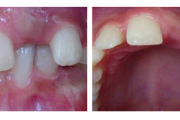

Vali sind huvitav pilt ja me näitame sellega seotud haigust ja sümptomeid